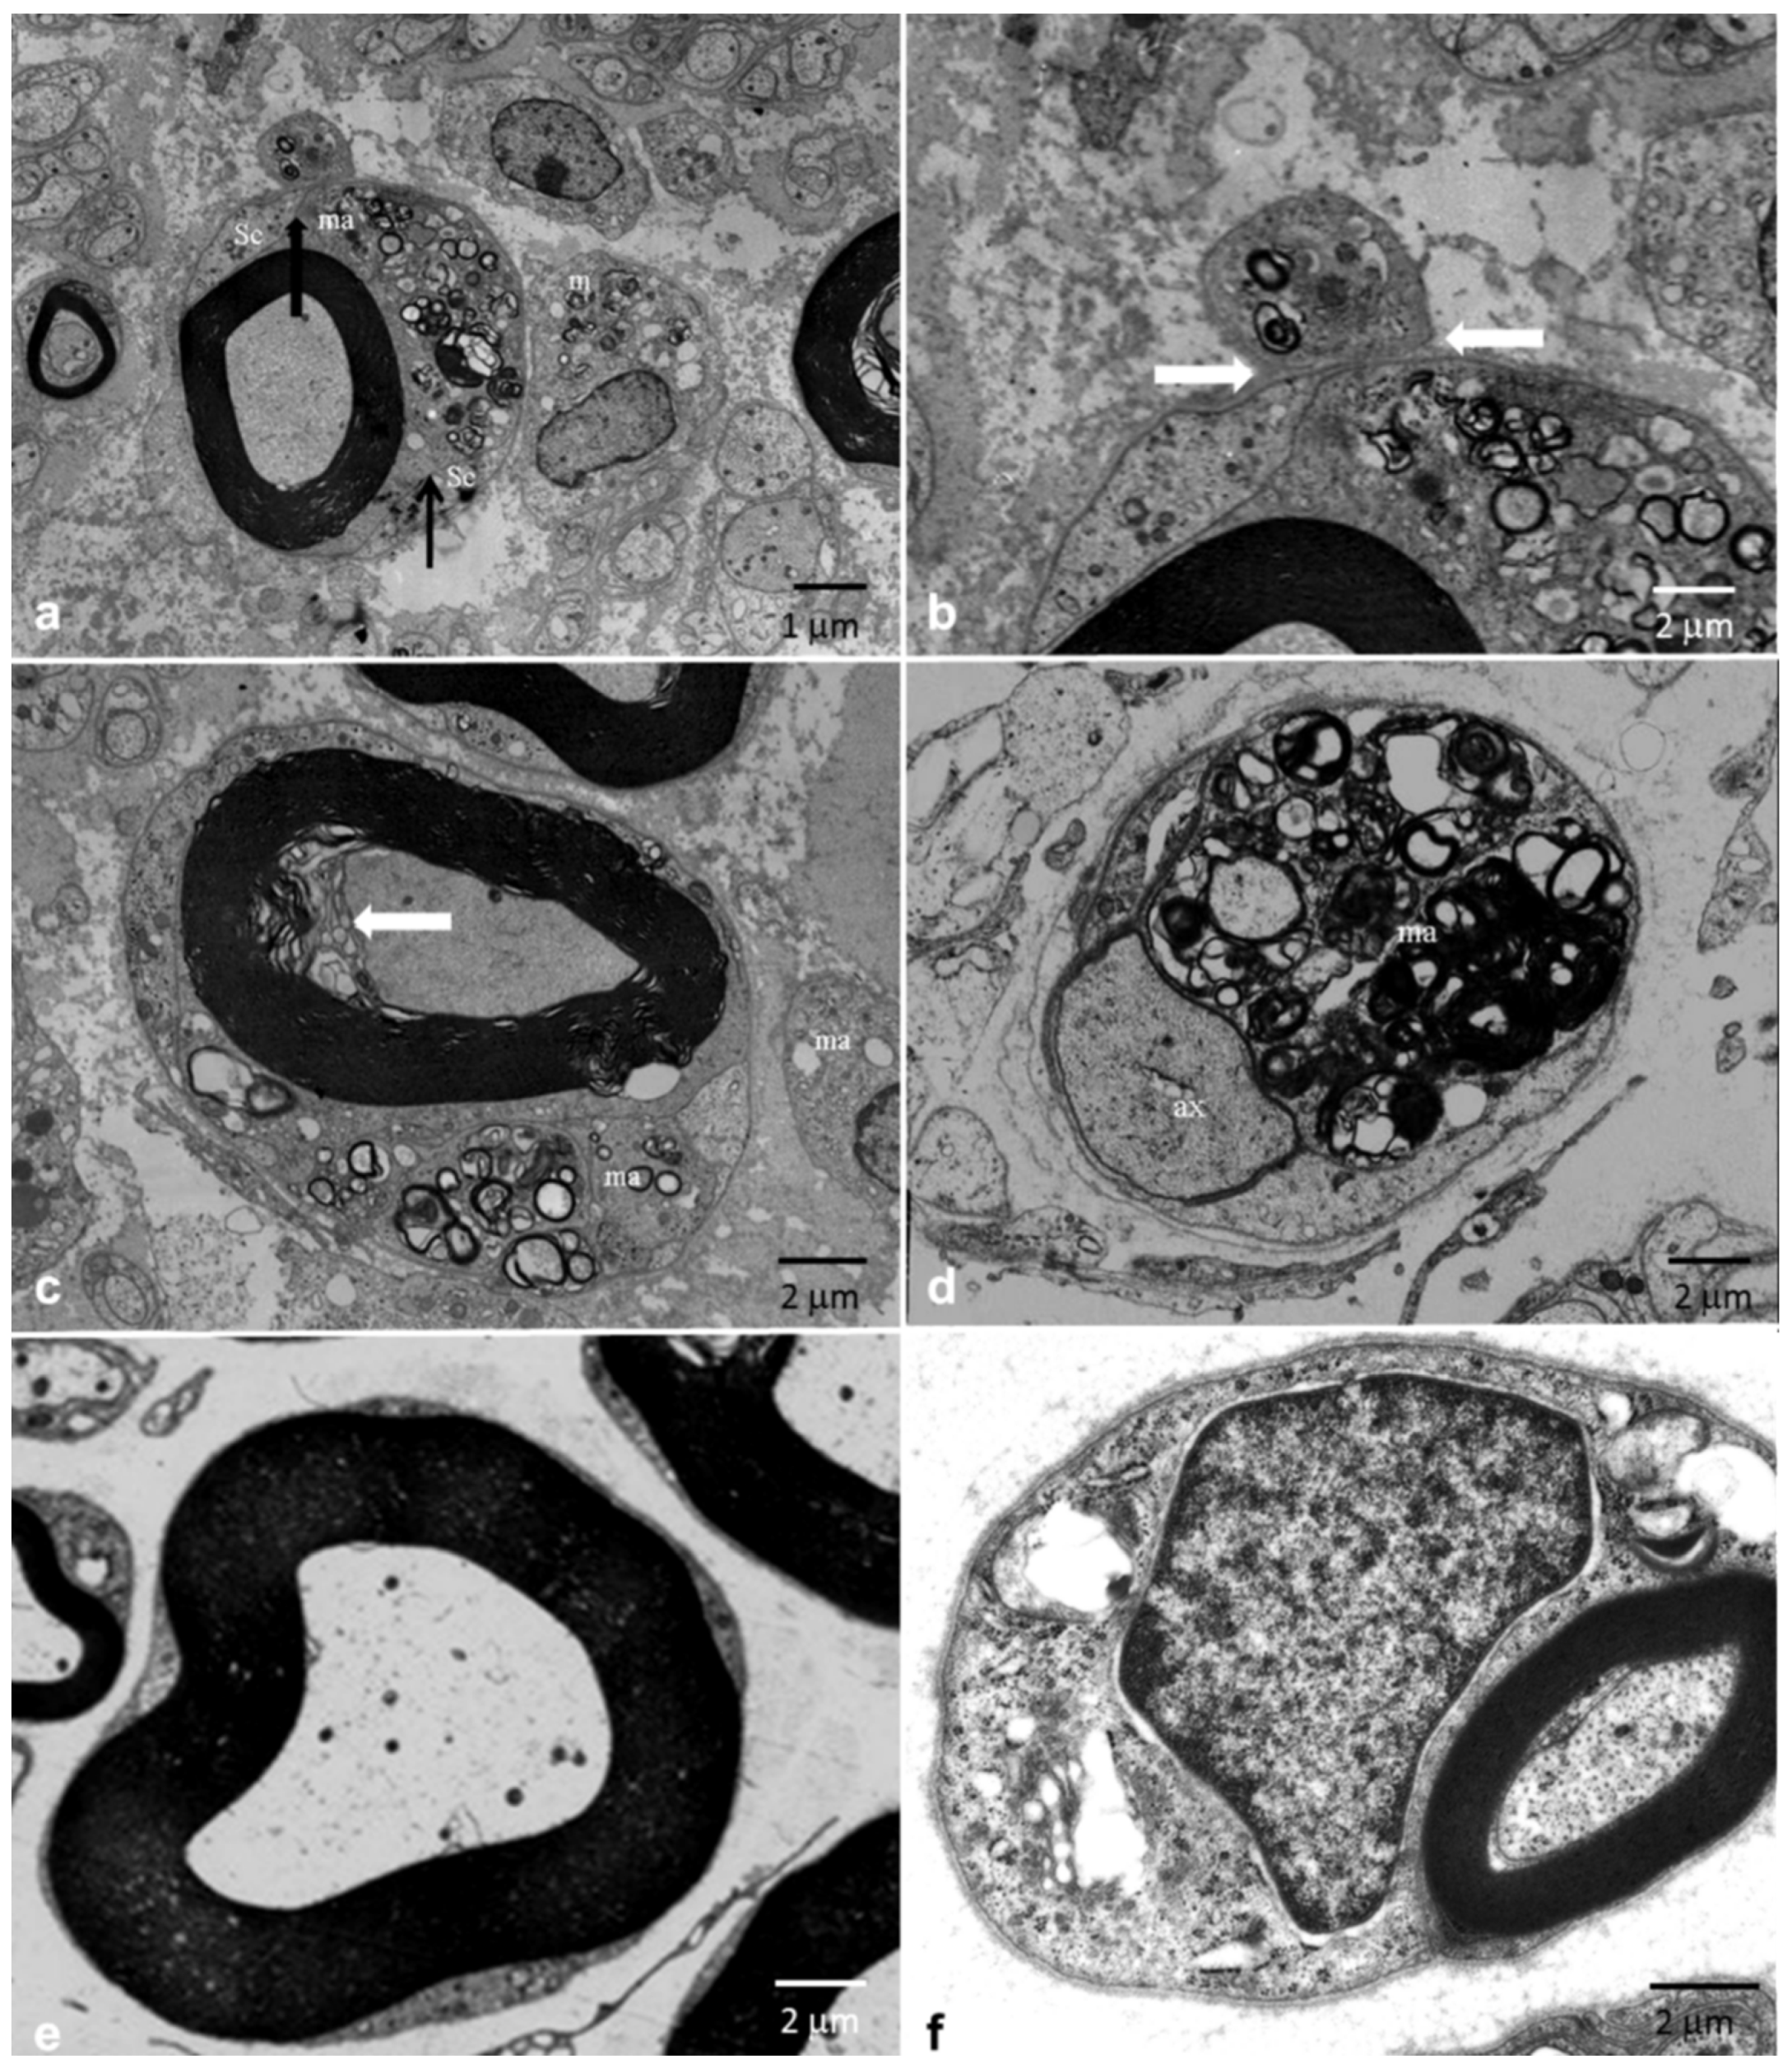

3.2. Pathological Results